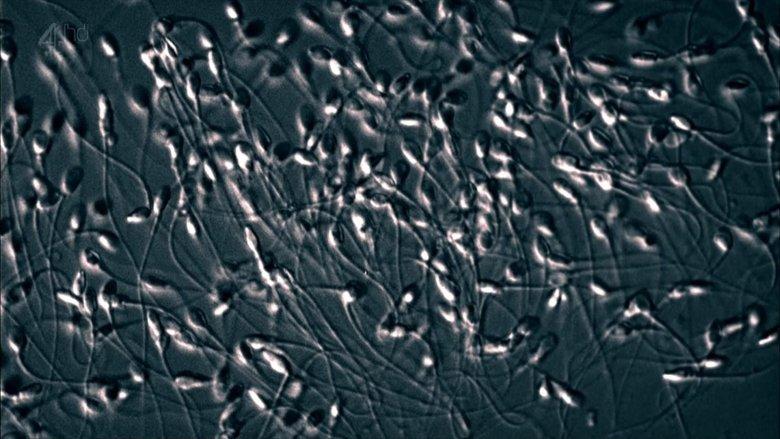

'The Great Sperm Race' tells the story of human conception as it's never been told before. With 250 million competitors, it is the most extreme race on earth and there can only be one winner.